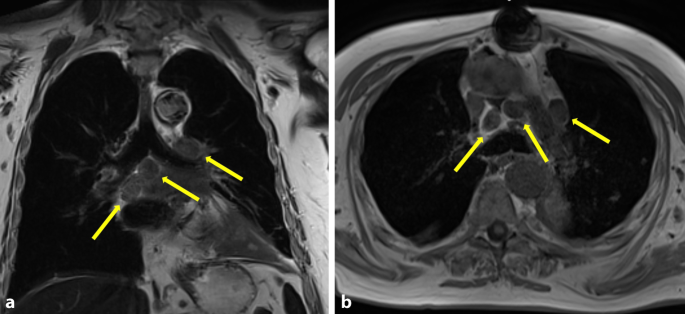

Abbildung 2b: Lungenhilus - Metastasenfrei

Moderne Bildgebung des Lungenhilus | Die Radiologie

Computertomografie | Moderne Bildgebung des Lungenhilus | springermedizin.de